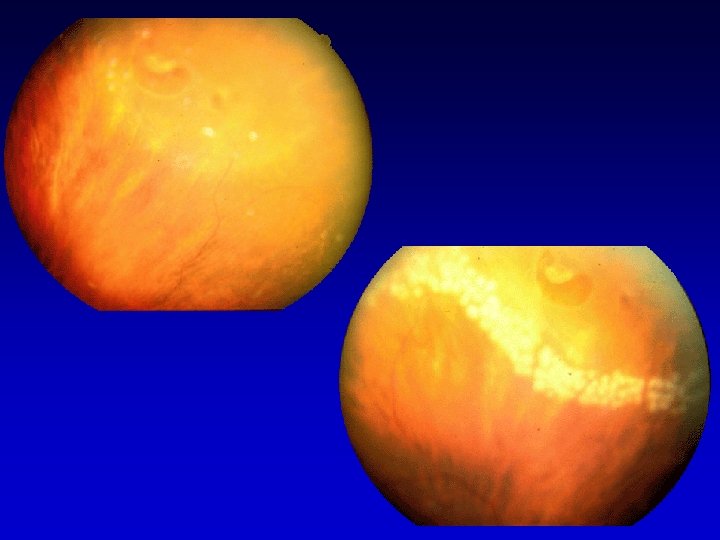

Classificazione delle alterazione retiniche nel diabete (Scuderi G. 1960) Forme pure Vasculopatia lieve Microaneurismi e emorragie puntiformi Retinite puntata A tipo prevalentemente emorragico A tipo prevalentemente degenerativo Vasculopatia marcata Gravissime emorragie retiniche e preretiniche con serie lesioni vasali specie venose Vasculopatia grave Invasione emorragica del vitreo Trombosi venosa diabetica Forme spurie od ibride Retinopatia diabetica-arteriosclerotica Retinopatia diabetica nefritica (iperazotemica-albuminurica gravidica) Retinopatia proliferante

CLASSIFICAZIONE RETINOPATIA DIABETICA NON PROLIFERANTE PROLIFERANTE AIRLIE HOUSE CLASSIFICATION MODIFICATA DA EARLY TREATMENT DIABETIC RETINOPATHY STUDY GROUP 1991